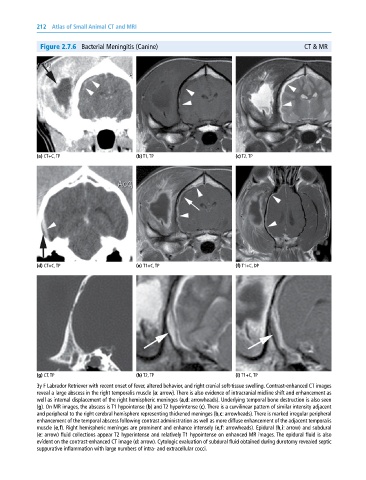

Figure 2.7.6 Bacterial Meningitis (Canine) CT & MR

(a) CT+C, TP (b) T1, TP (c) T2, TP

(d) CT+C, TP (e) T1+C, TP (f) T1+C, DP

(g) CT, TP (h) T2, TP (i) T1+C, TP

3y F Labrador Retriever with recent onset of fever, altered behavior, and right cranial soft‐tissue swelling. Contrast‐enhanced CT images

reveal a large abscess in the right temporalis muscle (a: arrow). There is also evidence of intracranial midline shift and enhancement as

well as internal displacement of the right hemispheric meninges (a,d: arrowheads). Underlying temporal bone destruction is also seen

(g). On MR images, the abscess is T1 hypointense (b) and T2 hyperintense (c). There is a curvilinear pattern of similar intensity adjacent

and peripheral to the right cerebral hemisphere representing thickened meninges (b,c: arrowheads). There is marked irregular peripheral

enhancement of the temporal abscess following contrast administration as well as more diffuse enhancement of the adjacent temporalis

muscle (e,f). Right hemispheric meninges are prominent and enhance intensely (e,f: arrowheads). Epidural (h,i: arrow) and subdural

(e: arrow) fluid collections appear T2 hyperintense and relatively T1 hypointense on enhanced MR images. The epidural fluid is also

evident on the contrast‐enhanced CT image (d: arrow). Cytologic evaluation of subdural fluid obtained during durotomy revealed septic

suppurative inflammation with large numbers of intra‐ and extracellular cocci.